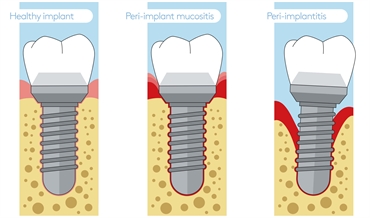

Peri implant mucositis is a very common problem observed with dental implants. Dental implants are put in place where the roots of the teeth are missing. The crown is then attached to the implant to compensate for missing natural teeth. Implant patients need to maintain the same level of dental hygiene with their artificial teeth as with natural teeth. The soft tissues or gums around the implant can become infected and inflamed if proper care is not taken. This lesion is known as peri-implant mucositis. If the infection persists then it damages the bone structure around the implant. This is known as peri implantitis and is one of the main reasons for implant failure.